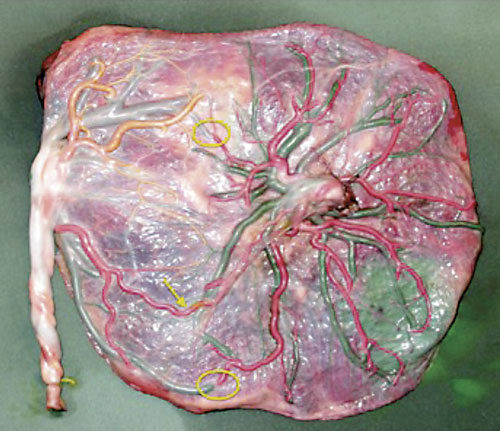

Tvillingtransfusionssyndromet. I Sverige görs därför fetoskopi i princip bara vid potentiellt letala tillstånd, framför allt vid tvillingtransfusionssyndrom. Kortfattat är syndromet en konsekvens av obalans i blodflödet i kommunicerande kärl mellan fostren – anastomoser i den gemensamma placentan – som alltid finns i en monokorionisk (monoplacentär, enäggstvilling-) graviditet Figur 1 [1].

Figur 1. Monokorionisk tvillingplacenta med kärlanastomoser. Blodkärlen ses med färgperfusion. Arteriovenösa anastomoser markerade med cirklar och arterio-arteriell anastomos markerad med pil.